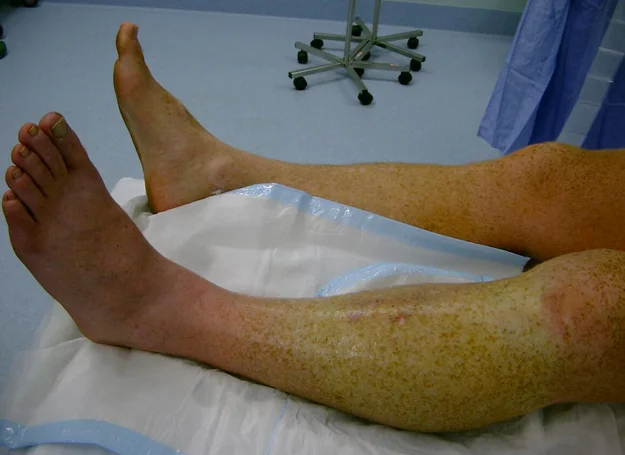

Clinical Picture - Look

- Shiny Swelling of compartment

- Pallor / or Dusky skin

- Blisters

- Clear fluid

- serosanguinous: severe

- Bloody: worst

Clinical Picture - Feel

- Tense

- Tender

- Paresthesia

- Weak Pulse ?

- Too late